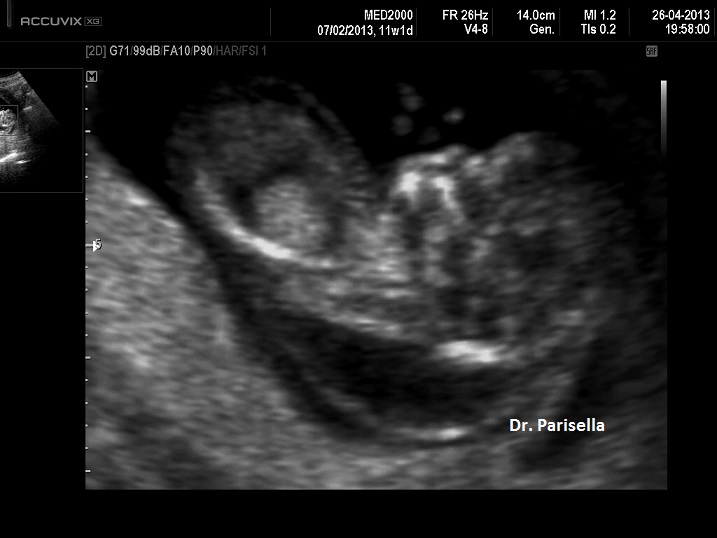

Il quadro malformativo conseguente alla sequenza ipo-acinesia-deformazione-fetale è legato ad una sequela di eventi caratteristici: a livello degli arti inferiori i gruppi muscolari più potenti sono gli estensori per cui gli arti inferiori saranno estesi e i piedi torti avranno un atteggiamento equino-varo; agli arti superiori prevalgono i muscoli flessori per cui le braccia saranno flesse davanti al torace, mani chiuse a pugno e in deviazione ulnare con clinodattilia; la paralisi del diaframma e dei muscoli respiratori sarà responsabile dell'ipoplasia toracica e polmonare; il blocco dell'articolazione temporo-mandibolare determina micrognazia; il blocco dei muscoli orbicolari determina microstomia. Ovviamente l'evento funzionale più evidente all'esame ecografico sarà rappresentato dall'assenza di movimenti attivi fetali.

La Diagnosi Ecografica Prenatale si basa quindi sulla presenza dei seguenti segni:

1) assenza di movimenti attivi fetali;

2) micrognazia;

3) artrogriposi degli arti;

4) anomalo atteggamento di mani e piedi: mano in deviazione ulnare, clinodattilia, piede torto equino-varo